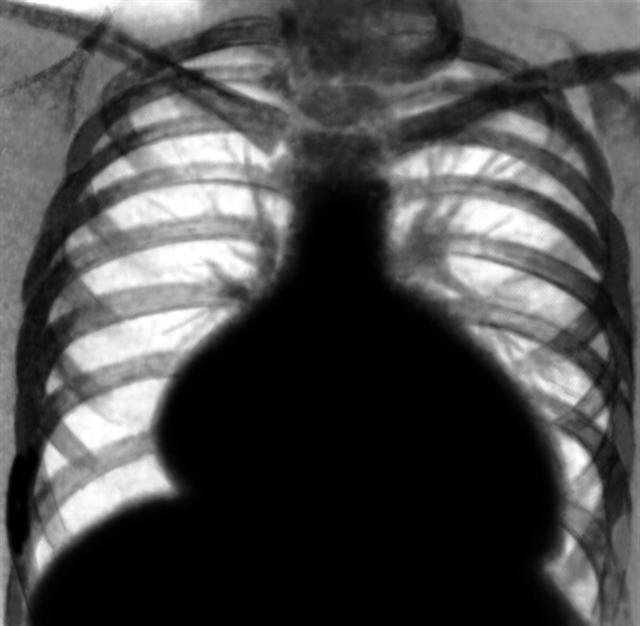

Рис. 2. Рентгенограмма грудной клетки больного с дилатационной кардиомиопатией: значительное увеличение тени сердца за счет расширения всех его полостей.